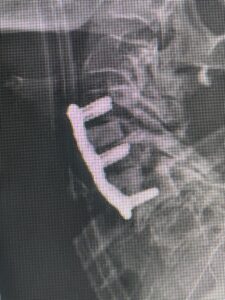

I specialize in and am very familiar with patients who have osteoporosis and require spinal surgery for degenerative lumbar disease. I am particularly interested in treating those osteoporotic patients with spinal stenosis and a concurrent spondylolisthesis or “slipped spine” or “slipped disc”. It is actually not the disc that slips in a spondylolisthesis, but one vertebra slips forward on the one below. As a result of this degenerative laxity the spine is signaled to make arthritis such as enlarged joints or thickened ligaments to compensate for the chronic instability that mainly contribute to narrowing of the spinal canal where the nerves travel. This is called spinal stenosis. Patients often see their MRI reports and note that they often have been described as having this aforementioned condition. I believe that perimenopausal, menopausal, and postmenopausal women (40-60 years of age) would benefit greatly because of their degree of activity and expectations from a new technology that my spine team is offering. However, this is not to say that men or women at any age who do require surgery would not benefit. A patient comes into the office and requires surgery to fix their slipped disc or spine and they say to me, “doctor but I have osteoporosis.” I tell them that we have available special coated screws that are designed for patients with osteoporosis that will do a much better job holding their bones together. Pedicle screws can be coated with a thin layer of hydroxyapatite (Fig 1)

(Fig 1) Hydroxyapatite Coated Pedicle Screw